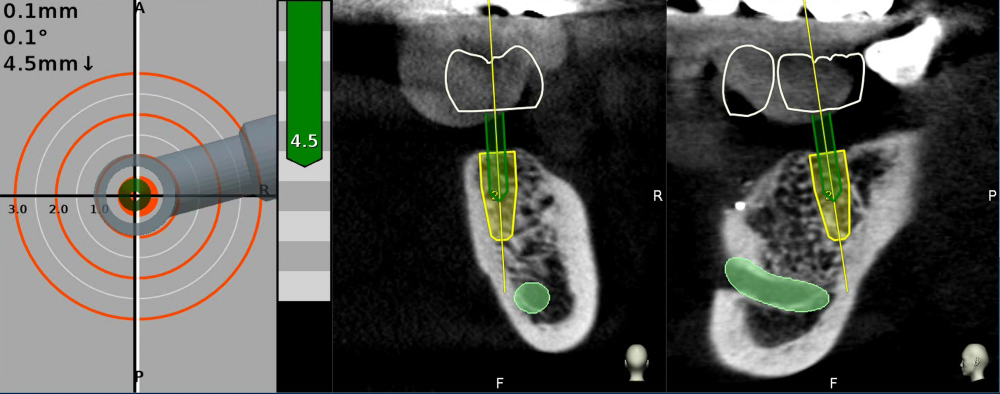

將數位資料匯入專業植牙規劃軟體,在電腦上進行精密的「虛擬手術」,預先設定好植體的最佳位置、角度、深度。

使用植牙導航,手術資訊與數位檔案同步顯示在電腦畫面上,使醫生能更快速、精準、安全的將植體放到目標位置。

▲使用導航技術,可以手術當下即時反映出植牙鑽針的角度、深度、位置等資訊,精準定位植體位置。